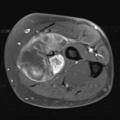

Gantzer J, Bouhamama A, Macagno N. Le diagnostic de sarcome relève d’une expertise d’équipe.  Rev Prat 2025 ;75(9) ;959 - 62.